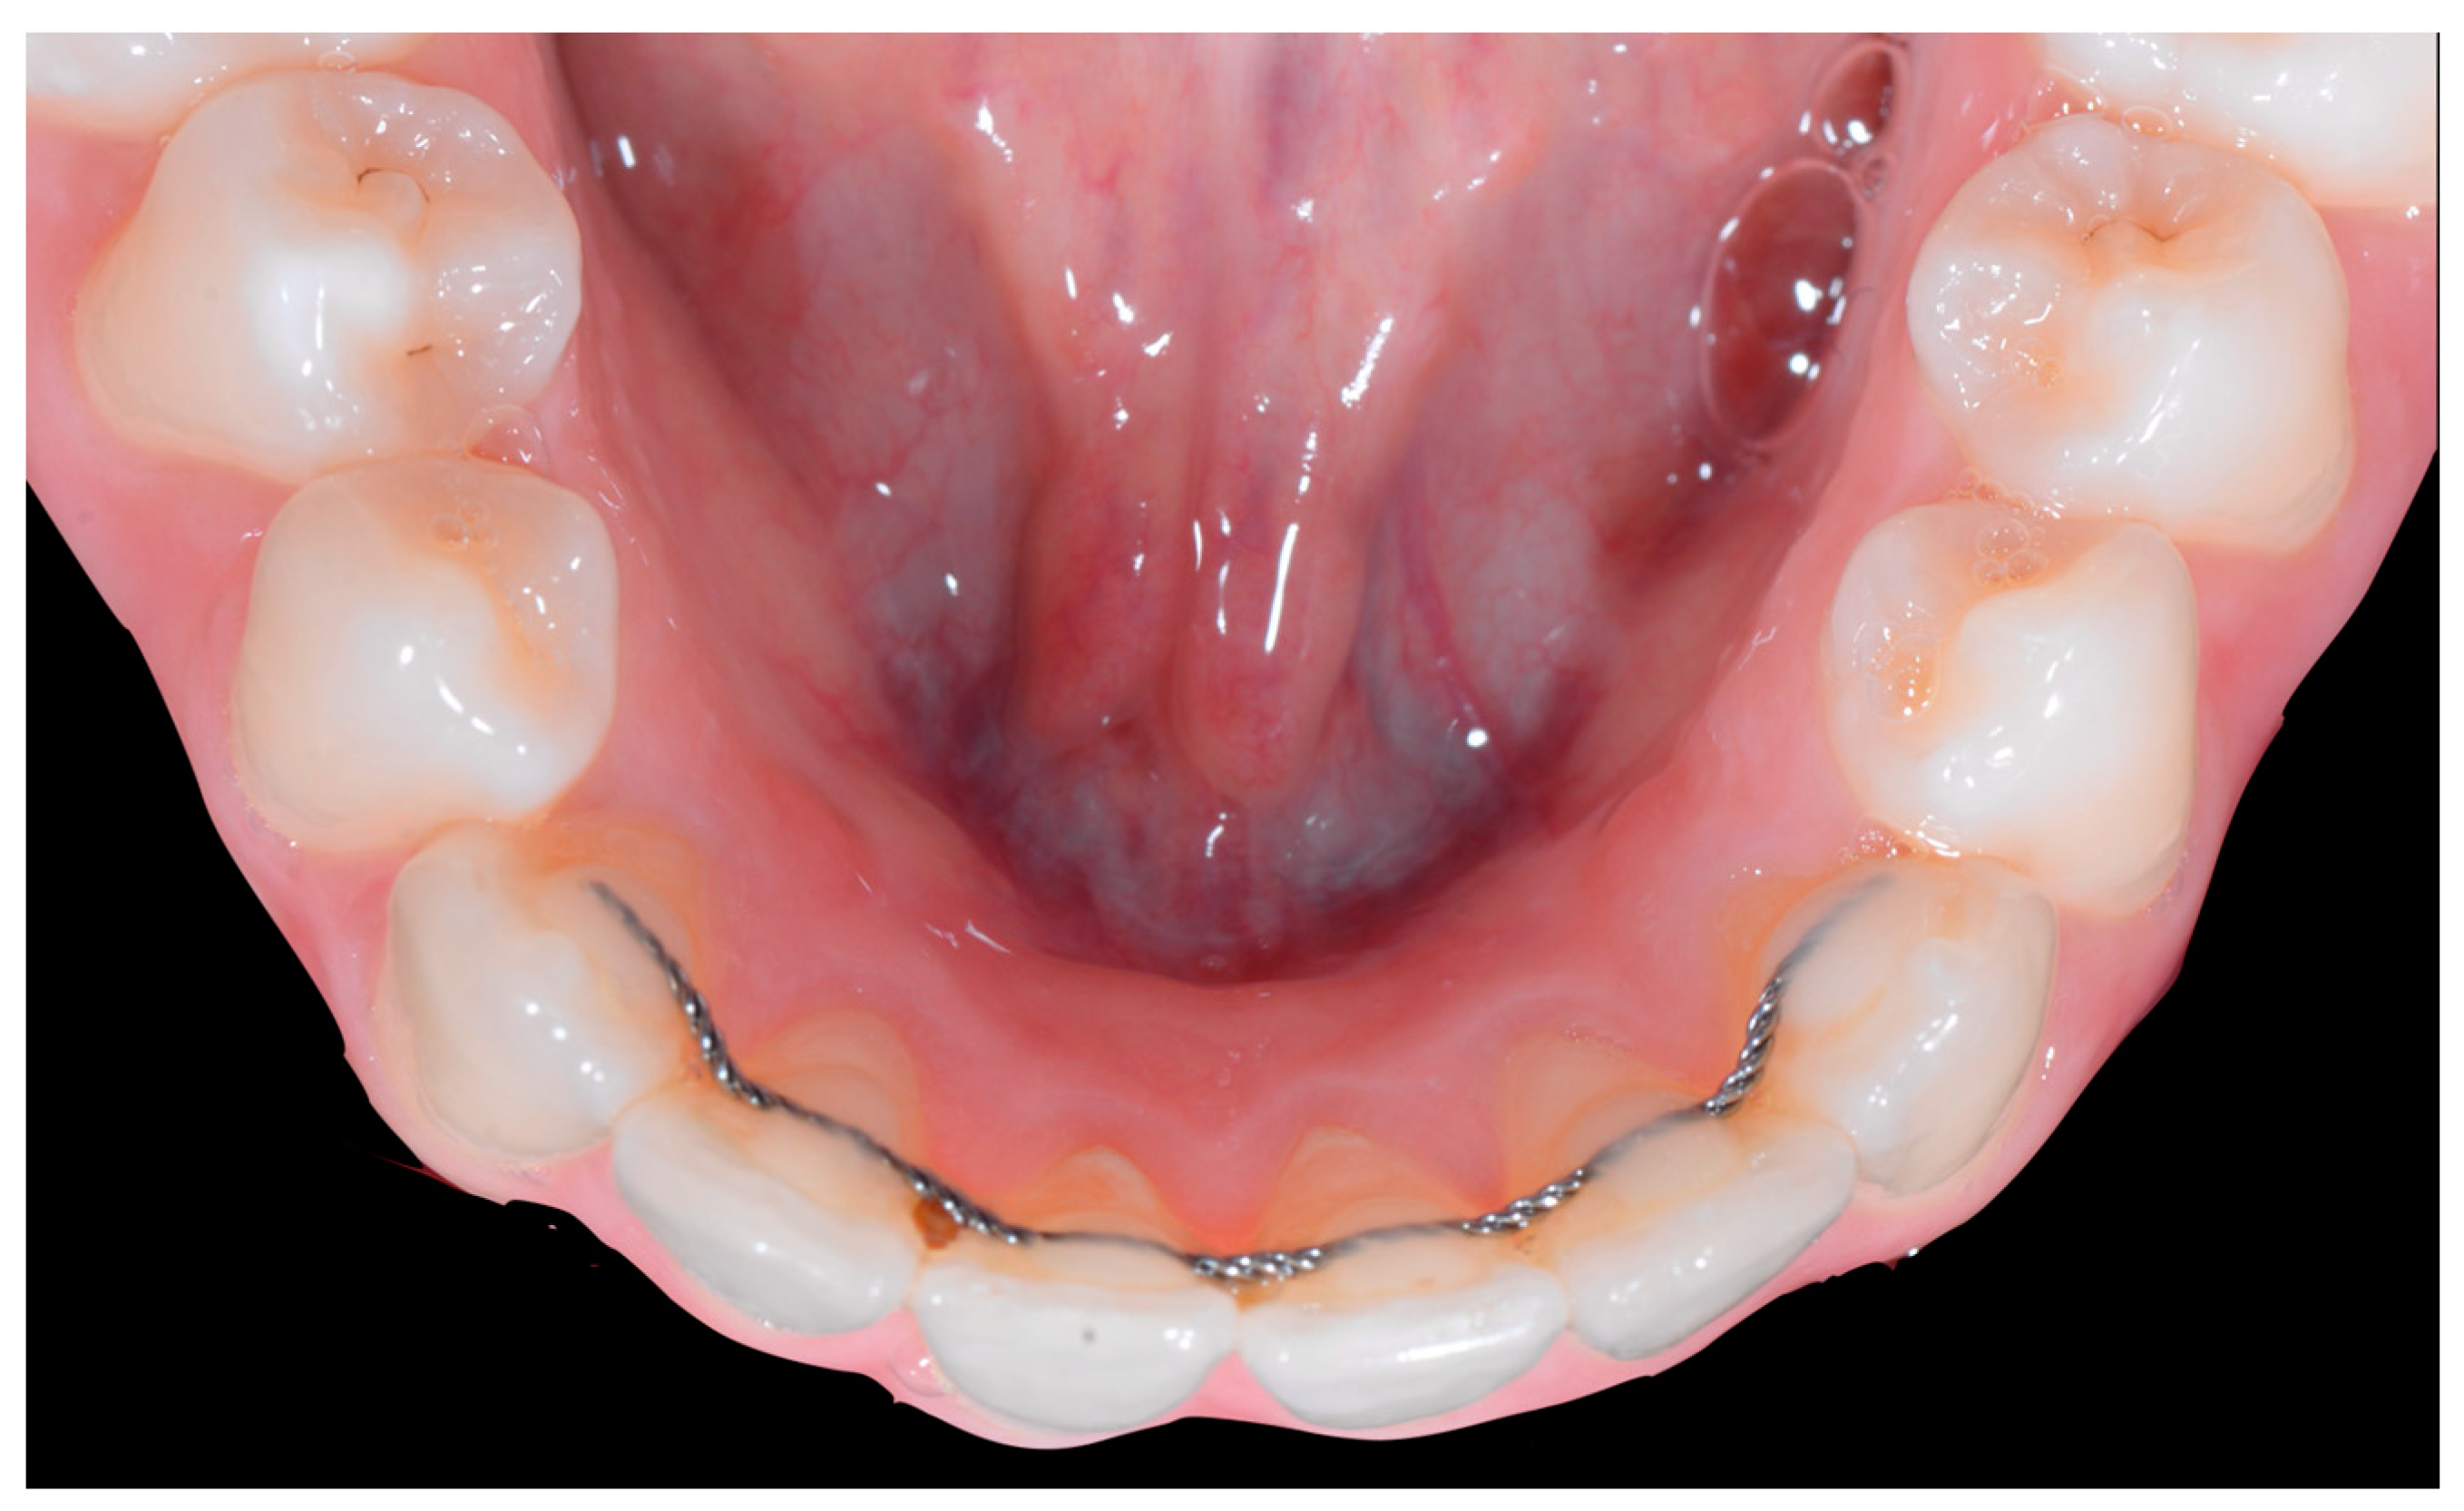

Occlusal views (Figure 4) confirmed the presence of a mandibular retainer which appears intact, without fracture or debonding, along its entire length. In addition, the vestibular surface of 41 appeared to have a difference in visibility from the adjacent teeth. Based on these clinical findings, wire syndrome starting on tooth 41, called the “X-effect” type, was suspected.

Early wire syndrome. Occlusal view.

The occlusal views provide additional relevant information (Figure 9 and Figure 10). A maxillary retainer was present on 11 and 21 only and a difference in visibility of the vestibular surfaces (differential torque) on these same teeth was noted.

Intermediate wire syndrome. Occlusal view.

In the mandible, the retainer was broken distal to 42 and, despite being intact on 33, this tooth had increased visibility of its vestibular surface compared to its contralateral tooth (differential torque). Finally, teeth 31 and 41 also showed a difference in the visibility of their vestibular surfaces (differential torque). Ultimately, the patient was diagnosed with an X-effect wire syndrome on 21, an X-effect wire syndrome on 41, and a Twist-effect wire syndrome on 33.

No retainer was present in the maxilla, only a residual mandibular retainer, still bonded to 32 and 42, was visible (Figure 14), as well as incisal crowding and a difference in the visibility of the buccal and root surfaces of 41 compared to the contralaterals. In this extreme clinical situation, a severe and terminal wire syndrome on tooth 41, the “X-effect” type, was observed.

Severe wire syndrome. Occlusal view.